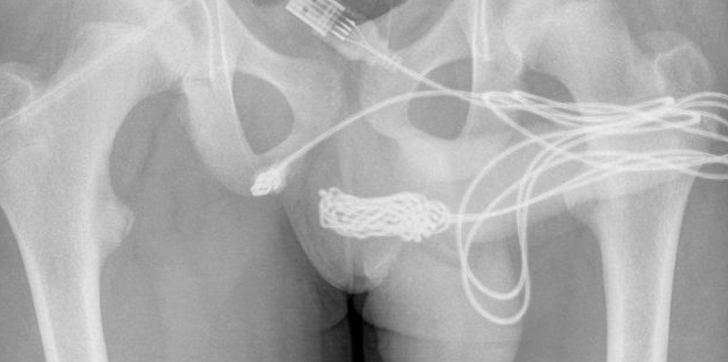

Un joven de Reino Unido terminó en la sala de urgencias luego de que se introdujera dentro de su miembro un cable USB con la intención de medir la longitud de su órgano reproductor.

Según el reporte médico, el joven se presentó a emergencias para el retiro del cable, presentando además una hematuria grave debido a que intentó extraerlo en su casa.

Tras llegar al centro hospitalario los médicos tuvieron que realizar una cistoscopía rígida y también una uretrotomía óptica, lo cual no tuvo ningún éxito debido al nudo existente en el cable.

Los doctores terminaron realizándole una incisión longitudinal penoescrotal sobre el cuerpo extraño palpable, realizándose una disección entre los tejidos profundos, donde dividieron el músculo bulboesponjoso, para luego sacar el cable a través del meato uretral externo.